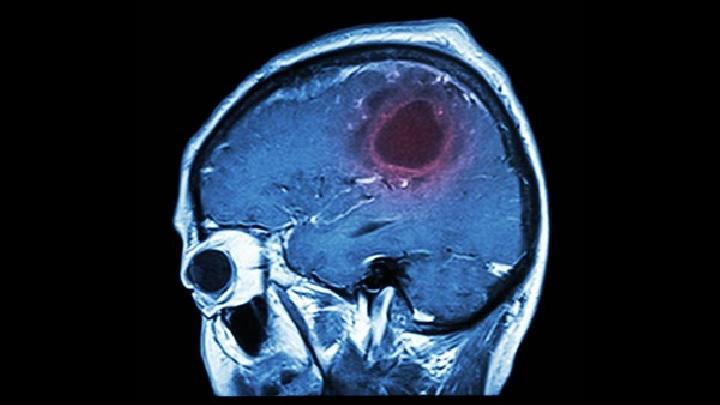

这种疾病是多因性的。由遗传、脑外伤、中毒后遗症、脑梗死、脑炎、脑膜炎、脑缺血、缺氧、脑血管畸形、脑肿瘤、脑中风、癫痫长期发作、烟酒过量、营养不良、甲状腺功能病变、脑动脉硬化、气体中毒、酒精中毒等引起脑实质性损伤和神经细胞萎缩、变形、消失,主要致病因素是脑血管长期慢性缺血。